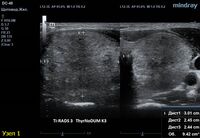

1) Узел занимает всю левую долю, но прорастает капсулу щитовидной железы (0 баллов), больше широкий чем высокий (0 баллов), не имеет кальцинатов (0 баллов), с ровным четким контуром (0 баллов), изоэхогенный (1 балл), тканевой структуры (2 балла). Количество баллов 3, ACRTi-RADS 3, ThyrNoDUMК3. Показана пункция в связи с большим диаметром узла (более 2,5см для Ti-RADS 3)